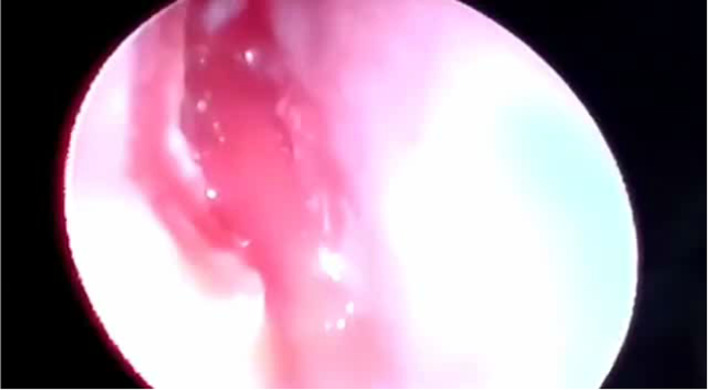

Intra-operative picture of the polyp

Endoscopic sinus surgery (sphenoidotomy) was done with polypectomy. There was a pale polypoidal mass measuring 4 cm between middle turbinate and septum, going to the sphenoidal ostium, and was found to be attached to the floor of the sinus, extending posteriorly into the choana (Fig. 2). The ostium was widened, polyp stalk was completely removed from the floor. The specimen was sent for histopathology (Fig. 3) and was reported to have polypoidal fragments of fibrocollagenous tissue focally lined by pseudostratified ciliated columnar epithelium, containing lymphocytes, plasma cells, & few mast cells suggestive of inflammatory polyp.

Fig. 2.